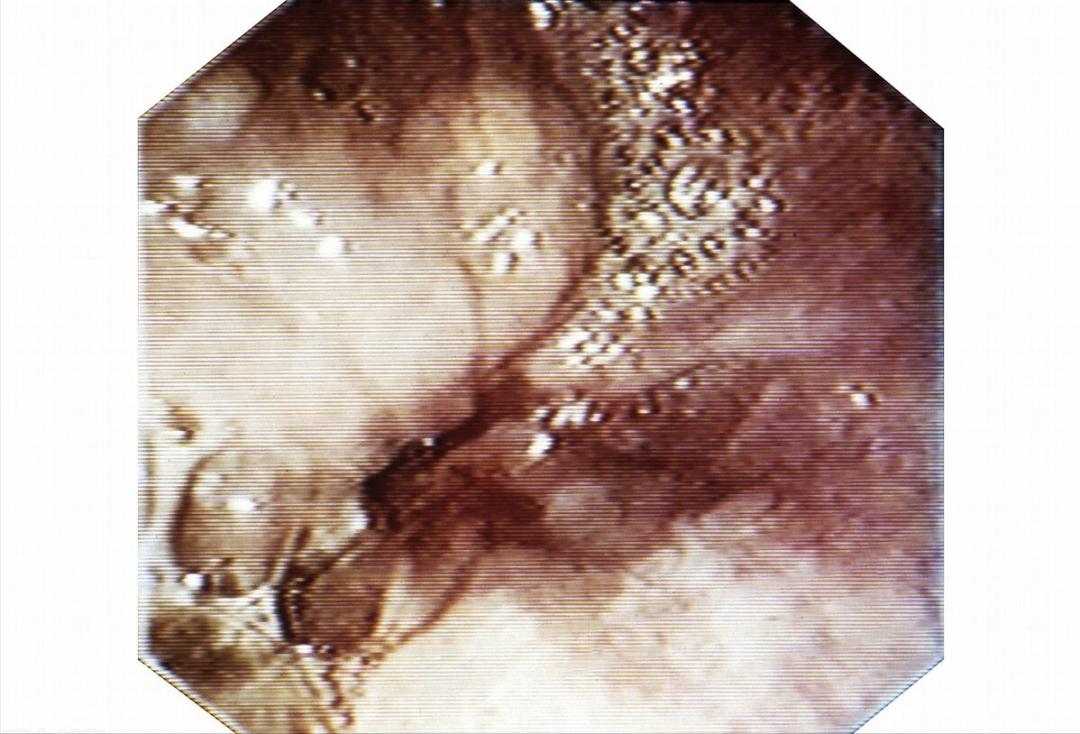

当天下午,结果出来了: II期食管癌,且肿瘤病变已经侵犯到食管肌层。

排除食管癌,做胃镜是性价比最高的,因为胃镜不仅能够诊断胃部问题,还能发现特别细小的早期食管癌,诊断率可以达到80%。